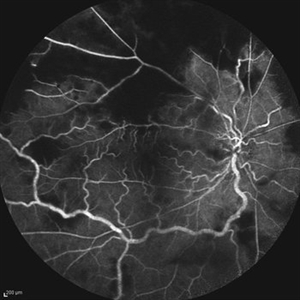

Behcet's Disease Behcet's DiseaseMar 13 2013 by Hamid Ahmadieh, MD Early phase FA of the right eye of a 23-year-old man with retinal vasculitis and branch retinal vein occlusion (BRVO) due to Behcet's disease . Photographer: Solmaz Shahmohammad, Negah Eye Center, Tehran Imaging device: Heidelberg Spectralis Condition/keywords: branch retinal vein occlusion (BRVO), retinal vasculitis

Behcet's Disease Behcet's DiseaseMar 13 2013 by Hamid Ahmadieh, MD Mid phase FA of the right eye of a 23-year-old man with retinal vasculitis and branch retinal vein occlusion (BRVO) due to Behcet's disease . Photographer: Solmaz Shahmohammad, Negah Eye Center, Tehran Imaging device: Heidelberg Spectralis Condition/keywords: branch retinal vein occlusion (BRVO), retinal vasculitis